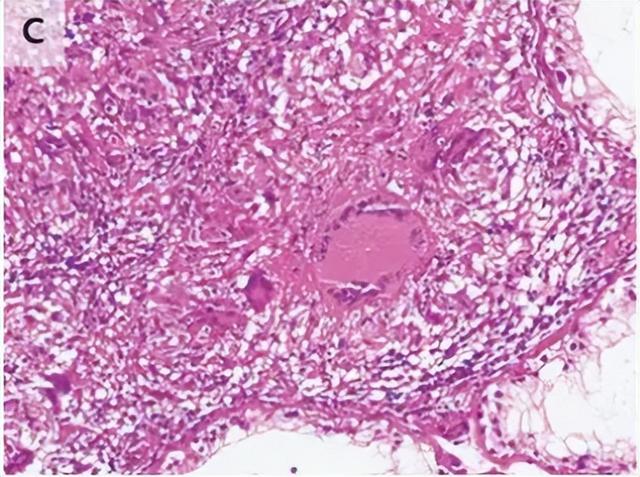

让人没有想到的是,病理检查结果出来,发现切出来的并不是癌症。王先生被切除睾丸的大体检查显示坏死结节,组织病理学检查显示肉芽肿性炎症伴甘酪样坏死和抗酸杆菌,这可是典型的结核症状啊。再看看实时聚合酶链式反应检测发现结核分枝杆菌。